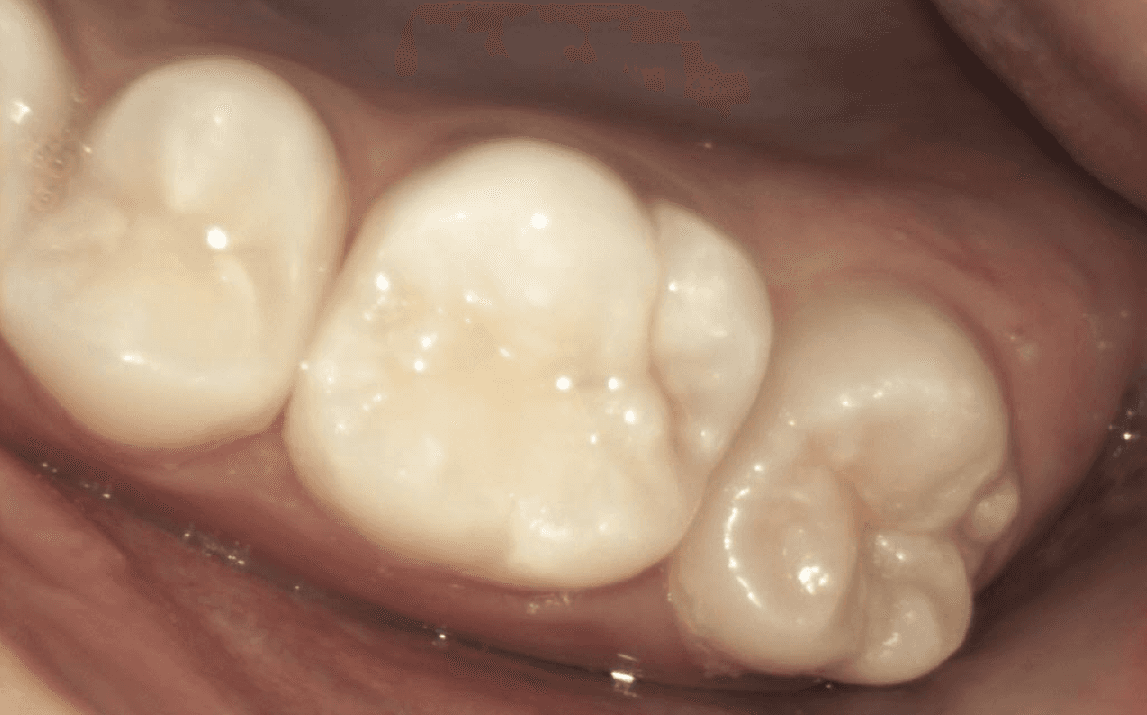

Take a look at the following example:

Decay was removed and very close to the pulp

Tooth restored seamlessly with composite resin